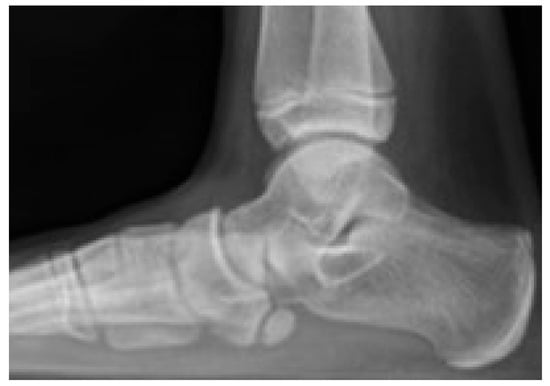

Radiograph (lateral view) of an 11-year-old female patient showing a flatfoot with a large accessory navicular bone.

In the case of the accessory navicular, the incidence of osteochondrosis is more frequent in females, with the most affected age group being between 12 and 15 years, especially following minor and major trauma [14]. The presence of an accessory navicular is commonly associated with flatfoot deformity (Figure 16). In many cases, a significant portion of the tibialis posterior tendon inserts onto the accessory ossicle rather than the main body of the navicular bone. This abnormal insertion may displace the tendon medially, contributing to hindfoot valgus alignment. Patients typically present with pain localized along the medial aspect of the foot. Prominence of the accessory navicular may lead to difficulties with footwear and the development of callosities. The clinical presentation may be insidious in onset or exacerbated by acute trauma to the foot or ankle. The mechanism of injury often mimics that of a medial ankle sprain, with abnormal tensile stress applied to the posterior tibialis tendon. A valgus stress event may result in fracture or separation of the ossicle from the navicular, causing instability and further contributing to the flatfoot deformity and prominence of the navicular complex. On physical examination, there may be palpable mobility of the accessory bone and marked tenderness over the medial border of the navicular. Symptoms are typically reproduced with passive forced eversion and resisted inversion of the foot.

Figure 16.

Radiograph of a 10-year-old male patient with flatfoot and a prominent accessory navicular bone.

Standard radiographs and Computer Tomography (CT) scans commonly demonstrate a well-ossified accessory bone adjacent to the proximal medial margin of the navicular (Figure 17). In some cases, the accessory navicular is not only a source of localized symptoms but may also predispose the tibialis posterior tendon to chronic or acute injury. Tendinous fibers usually insert onto both the navicular and the accessory ossicle, and this atypical anatomy may increase the risk of tendon dysfunction, particularly in athletes. MRI in such individuals may reveal edema within the accessory navicular, indicative of chronic mechanical stress and overuse [63] (Figure 18).